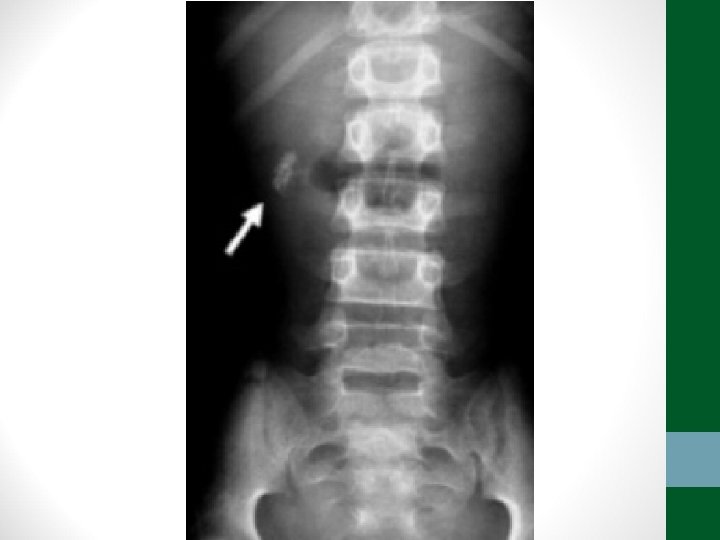

Exames de Imagem • Abdome Agudo Inflamatório: • Radiografia simples de abdome: decúbito, ortostase e cúpulas diafragmáticas • USG Abdome total é diagnóstico na maioria dos casos • TC de abdome com contraste VO e EV se USG não esclarecer ou em forte suspeita de diverticulite aguda ou pancreatite aguda grave

Exames de Imagem • Abdome Agudo Perfurativo: • Radiografia simples de abdome: decúbito, ortostase e cúpulas diafragmáticas • USG Abdome não ajuda! • TC de abdome com contraste VO e EV se Raio-X não esclarecer

Exames de Imagem • Abdome Agudo Obstrutivo: • Radiografia simples de abdome: decúbito, ortostase e cúpulas diafragmáticas • USG abdome não ajuda! • TC Abdome com contraste VO e EV se não houver resolução em 48 h de tratamento clínico ou de acordo com suspeita clínica

Exames de Imagem • Abdome Agudo Vascular: • Radiografia simples de abdome: decúbito, ortostase e cúpulas diafragmáticas • USG abdome não ajuda! • TC Abdome com contraste EV e VO – angio. TC (fase arterial e portal) é o melhor exame

Exames de Imagem • Abdome Agudo Hemorrágico: • Radiografia simples de abdome: decúbito, ortostase e cúpulas diafragmáticas (apenas para descartar outras causas) • USG Abdome é o exame mais importante, pode ser necessária USG transvaginal • TC de Abdome em casos selecionados